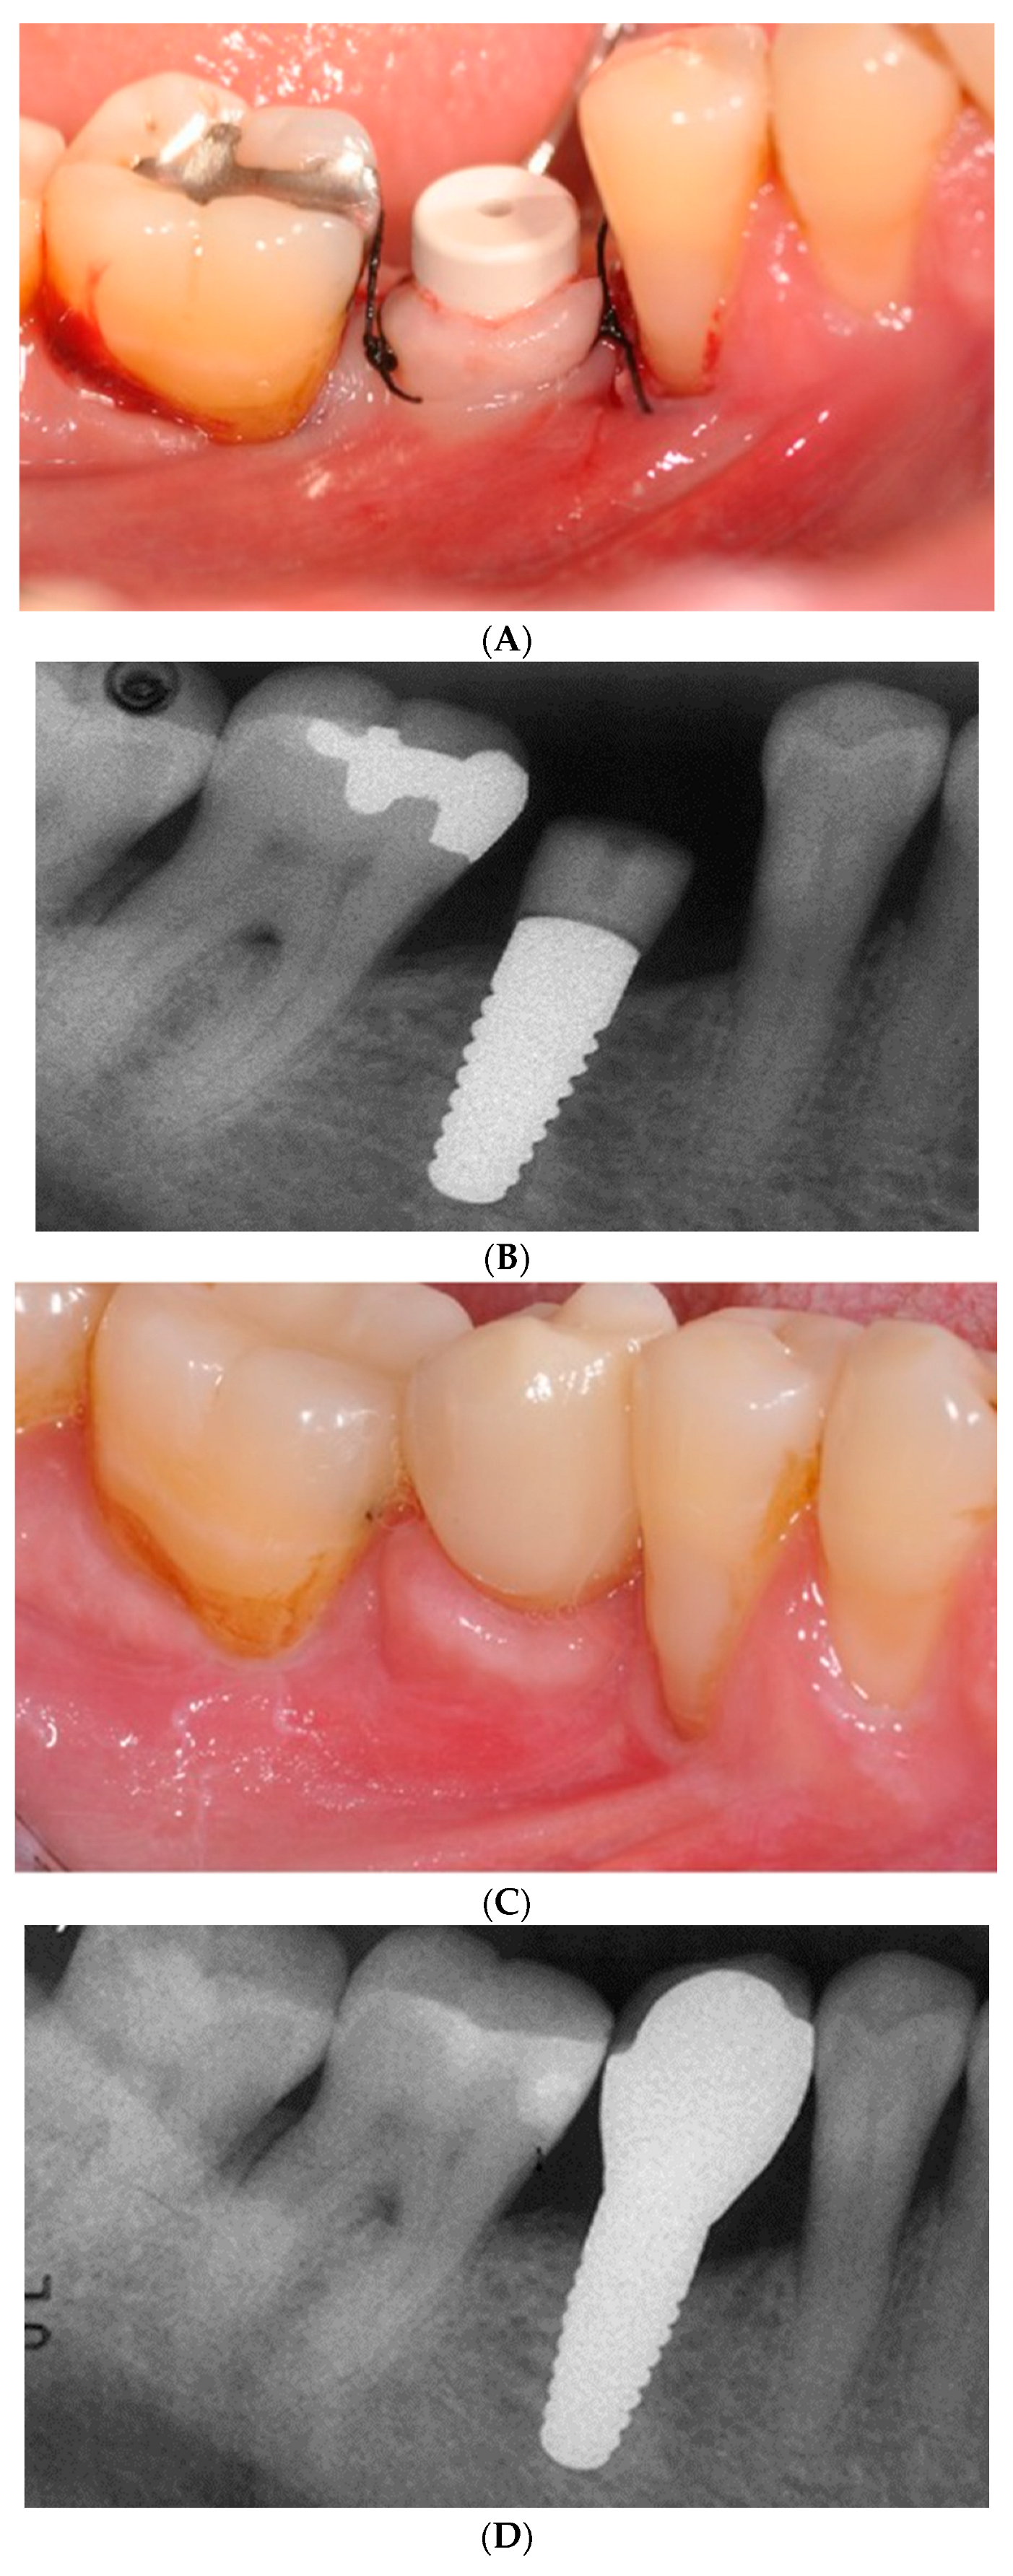

Figure 4. A. Two-piece zirconia implant with healing abutment in place. B. Radiograph of two-piece zirconia implant with healing abutment in site #29. C. Definitive restoration on two-piece zirconia implant. D. Radiograph of definitive crown on two-piece zirconia implant.